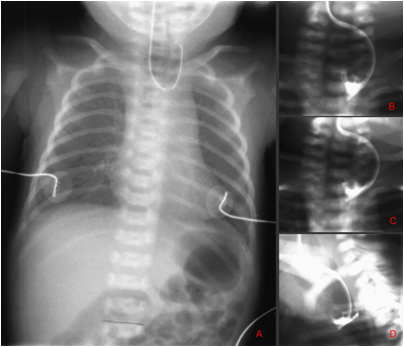

1.从口鼻插入F8号导尿管受阻,不能进入胃内。

2.颈、胸、腹正侧位X线摄片示导管卷曲或造影显示食道近端盲袋。

EA/TEF术后常见并发症和治疗

吻合口狭窄